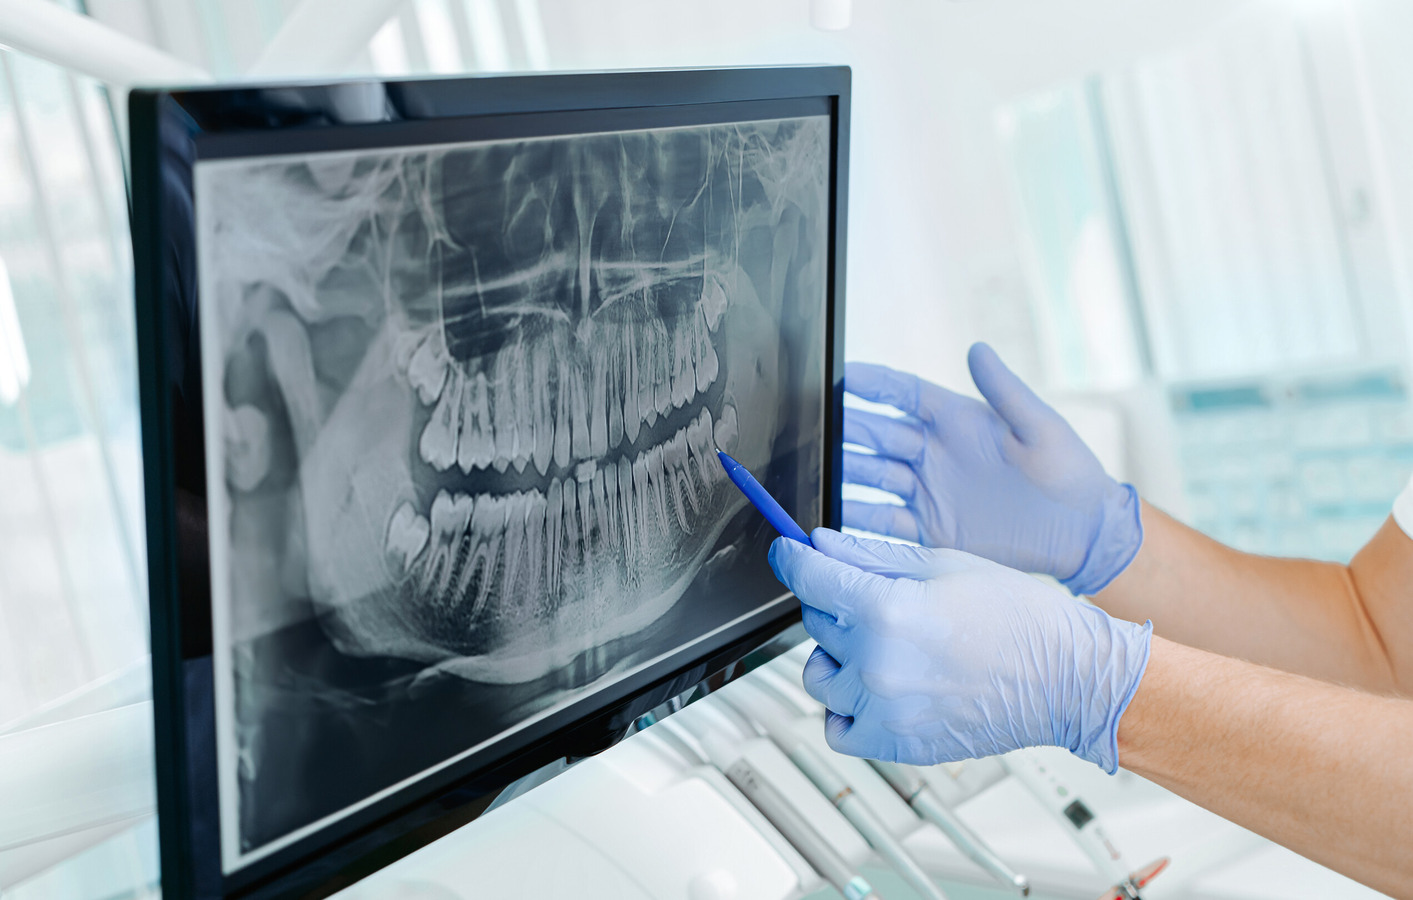

Dental X-rays are essential for orthodontics because they let the orthodontist see what’s happening beneath the surface of your teeth and gums, which a simple visual exam or even a 3D scan can’t reveal. Specifically, X-rays help orthodontists:

Assess tooth position & development: X-rays show the exact alignment of teeth, root development, and whether any teeth are impacted (stuck under the gums) or coming in at unusual angles.

Evaluate jaw growth & structure: X-rays provide insight into the bones of the jaws and face, helping diagnose skeletal issues like overbites, underbites, or asymmetries that braces or other orthodontic treatments need to address.

Check for missing or extra teeth: They identify congenitally missing teeth or extra (supernumerary) teeth, which can affect the growth and development of the permanent teeth. Orthodontists may also use X-rays to assess the positions of wisdom teeth and predict how they will eventually impact treatment.

Monitor tooth and root health: X-rays can detect root resorption, cysts, or other problems that might affect long-term tooth health, movement, or stability during treatment.

Plan safe, effective treatment: Accurate diagnosis from X-rays helps orthodontists develop a treatment plan that minimizes complications and maximizes long-term results. This is the ultimate purpose of dental X-rays, and why our orthodontists insist on them.

Dental X-rays provide orthodontists with the full picture needed to move teeth safely, correct bite problems, and ensure your smile remains healthy and stable for years to come.